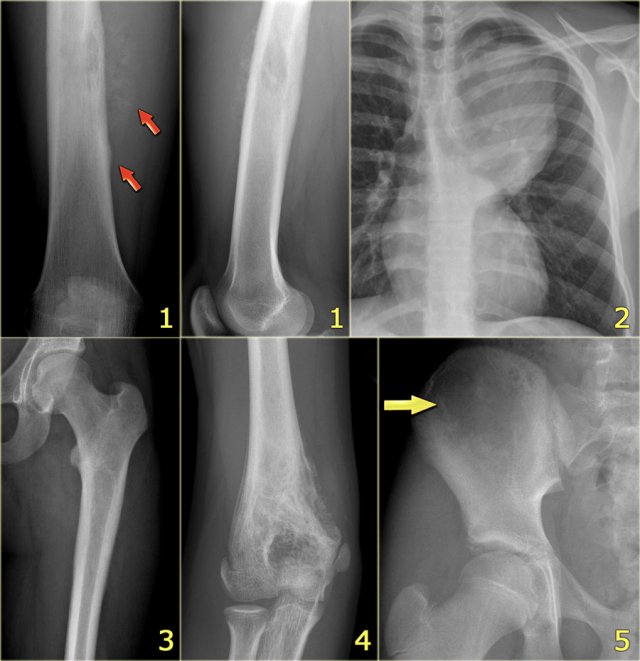

ABC (6) - atypical case

On the left two different patients with an intracortical or subperosteal osteolytic well-defined lesion in the tibia.

The lesion on the far left was thought to be an adamantinoma because of the localisation in the anterior tibial cortex.

At biopsy it proved to be an ABC.

The image on the right is an adamantinoma.

Adamantinoma

key facts:

• Rare low-grade malignant lesion, exclusively found in the diaphysis of the anterior cortex of the tibia.

• Adamantinoma may present as a solitary focus or multicentric lucencies

• May extend into the marrow cavity.

• Plain radiographs and CT show cortical lucencies combined with sclerosis.

• On MRI, the lesion is lobulated with high signal intensity on T2-weighted images and strong enhancement after Gd-DTPA.

• Main differential diagnosis: fibrous dysplasia.

Adamantinoma (2)

Young patient with a lobulated lytic lesion within the anterior cortical bone of the proximal tibia.

There is a second lucency separately more proximal within the cortical bone.

Axail CT image prior to biopsy demonstrates the lytic appearance of the lesion within the thickened cortical bone.

In the differential diagnosis could have been chondromyxoid fibroma or fibro-osseous lesion, however, the separate cortical lesion strongly suggests adamantinoma, which is almost exclusively found in the tibia and often multicentric.